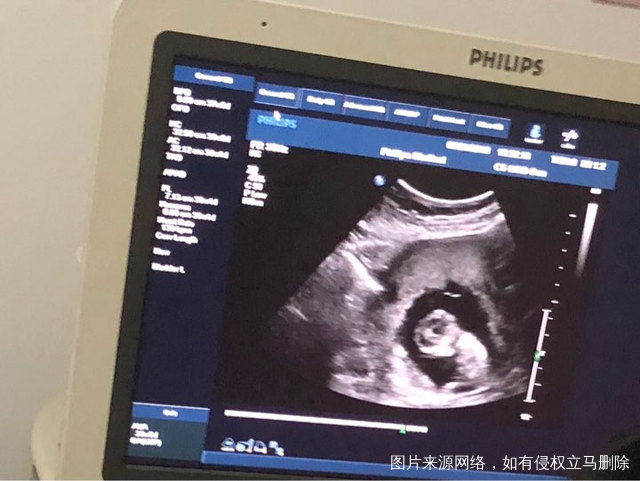

一次成功,12周,NT顺利通过

今天12周NT,顺利通过,第一次看到我的大头宝宝,已经长到52毫米了,第一次听到胎心,像小火车一样呼啦呼啦,这种感觉好神奇,生殖中心顺利毕业,以后转产科了